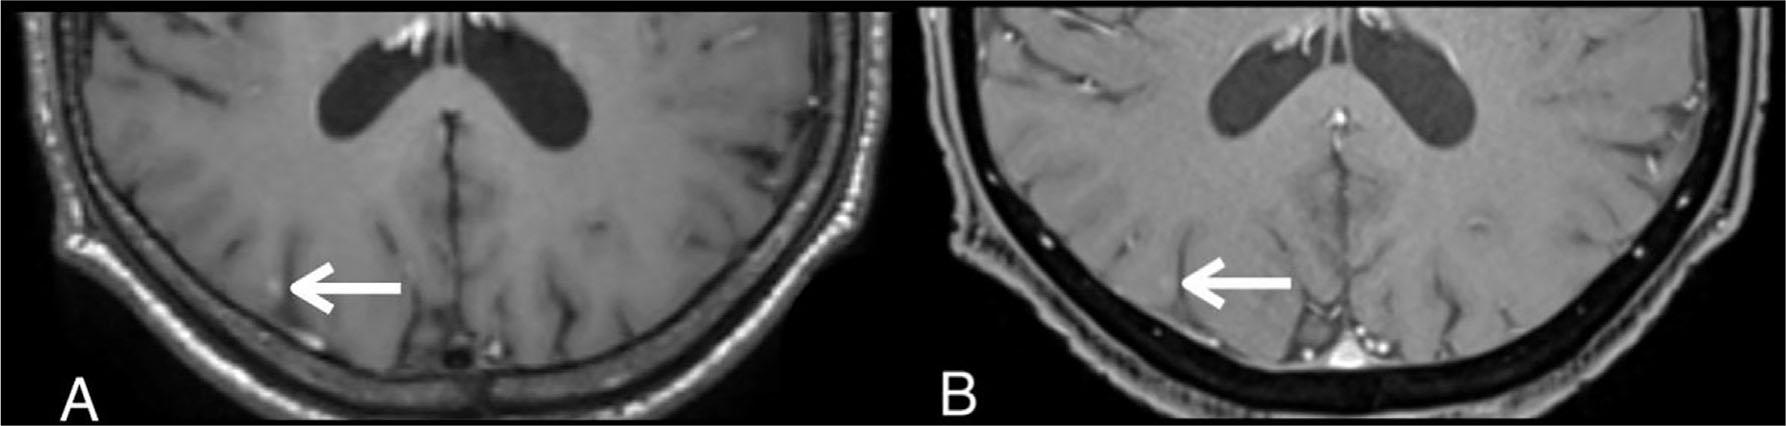

Figure 1

A 58-year-old lung cancer patient with a brain metastasis in the right occipital lobe (white arrow) that was missed by readers on contrast-enhanced 3D T1-weighted VIBE on a separate reading. Axial contrast-enhanced 3D T1-weighted SPACE (A) shows higher contrast enhancement compared with axial contrast-enhanced 3D T1-weighted VIBE (B).

Another different characteristic between spin-echo-based sequences and gradient-echo-based sequences is the signal intensity of the flowing blood [7]. The signal intensity of the flowing blood in SPACE and other spin-echo-based sequences is black (i.e., signal void), while the signal intensity of the flowing blood in MPRAGE and VIBE which are gradient-echo sequences is white (i.e., flow-related enhancement). The high signal intensity in the blood vessels may confuse the reader and obscure the high signal intensity in enhancing lesions. We believed that the distinct characteristics of the SPACE and VIBE sequences have partly induced the discrepancy in the number of detectable lesions in the first-level analysis. This study found that some of the discrepancies in the number of the detectable parenchymal enhancing lesions on each sequence during the separate readings were due to human error. Those lesions were missed on the separate reading but were visible on both sequences on head-to-head analysis. The source of the discrepancies occurred because the enhancing lesions were less conspicuous, looked like a vascular structure, located near a vascular structure, or had a very tiny size (Figures 1 and 2). The obscured lesions due to susceptibility signal loss were not observed in this study.